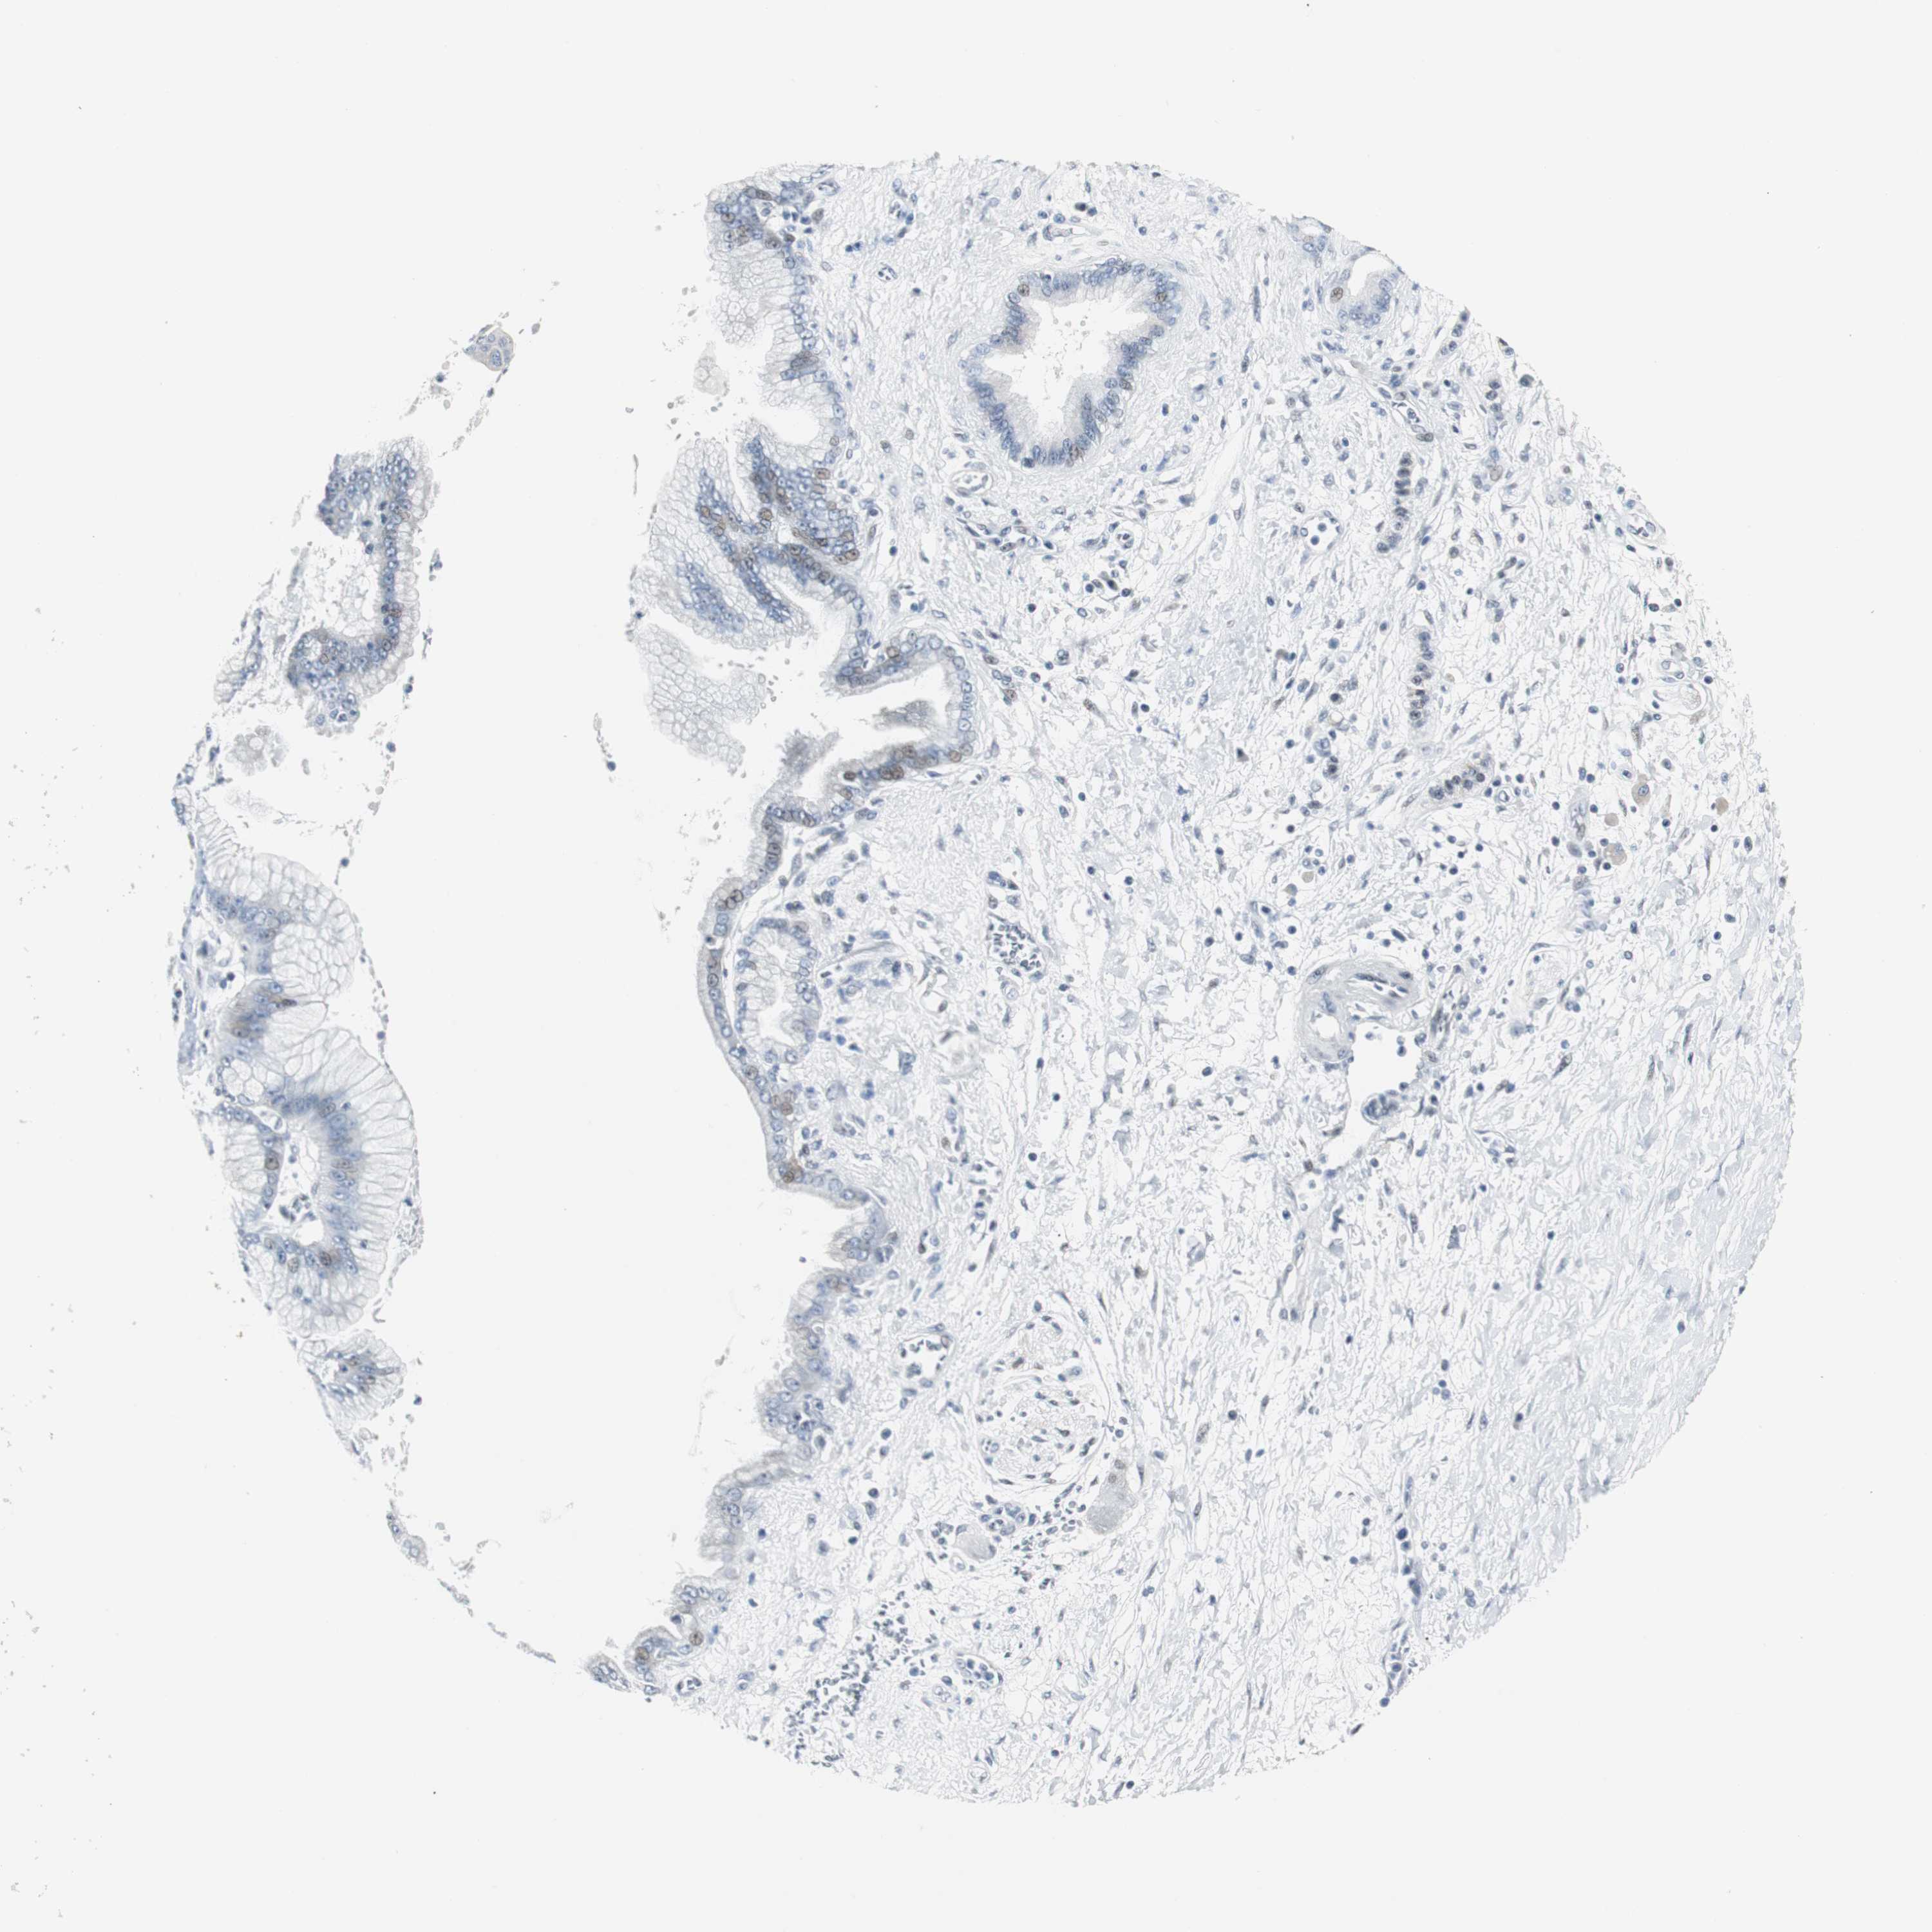

PANCREATIC CANCER - Protein expressioni

A mouse-over function shows sample information and annotation data. Click on an image to view it in a full screen mode. Samples can be filtered based on level of antibody staining by selecting one or several of the following categories: high, medium, low and not detected. The assay and annotation is described here.

Note that samples used for immunohistochemistry by the Human Protein Atlas do not correspond to samples in the TCGA dataset.

Antibody stainingi

Antibody staining in the annotated cell types in the current human tissue is reported as not detected, low, medium, or high, based on conventional immunohistochemistry profiling in selected tissues. This score is based on the combination of the staining intensity and fraction of stained cells.

Each image is clickable and will lead to virtual microscopy that enables deeper exploration of all samples and also displays staining intensity scores, fraction scores and subcellular localization as well as patient and tissue information for each sample.

Antibody HPA005544

Antibody CAB004508

Staining

High

Medium

Low

Not detected

Intensity

Strong

Moderate

Weak

Negative

Quantity

>75%

75%-25%

<25%

None

Location

Nuclear

Cytoplasmic/membranous

Cytoplasmic/membranous,nuclear

Adenocarcinoma, NOS

Adenocarcinoma, metastatic, NOS